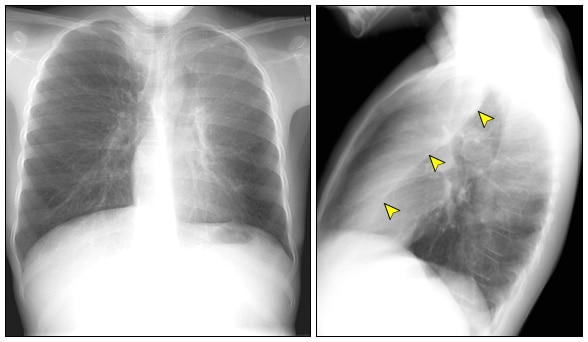

Quando o médico suspeita de atelectasia, a investigação começa com exames de imagem. O mais comum é a radiografia de tórax. Ela pode mostrar áreas do pulmão que parecem opacas, indicando a falta de ar.

Para um diagnóstico mais detalhado, a tomografia computadorizada (TC) de tórax é excelente. Ela oferece imagens mais nítidas e ajuda a identificar a causa exata do colapso, como um tumor ou um coágulo de muco.